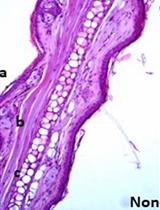

Mouse models have demonstrated utility in delineating the mechanisms underlying many aspects of malaria immunology and physiology. The most common mouse models of malaria employ the rodent-specific parasite species Plasmodium berghei, P. yoelii, and P. chabaudi, which elicit distinct pathologies and immune responses and are used to model different manifestations of human disease. In vitro culture methods are not well developed for rodent Plasmodium parasites, which thus require in vivo maintenance. Moreover, physiologically relevant immunological processes are best studied in vivo. Here, we detail the processes of infecting mice with Plasmodium, maintaining the parasite in vivo, and monitoring parasite levels and health parameters throughout infection.